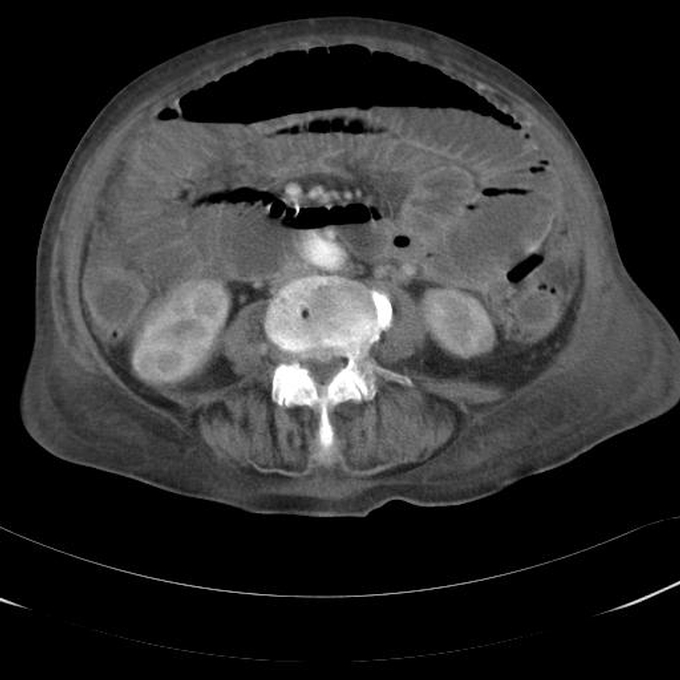

Er stellt den tiefsten Punkt der Bauchhöhle im aufrechten Stand dar und ist ein wichtiger Bereich für die Ansammlung von Flüssigkeiten bei bestimmten Erkrankungen. Beim Mann entspricht diese Bauchfellnische dem spaltförmigen Raum zwischen Rektum und Blase, genannt Excavatio.

Deshalb wird er im Medizinerjargon auch als "Schlammfang der Bauchhöhle" gehandelt Die Douglas-Punktion wird heute (2023) nur noch selten zur Keimbestimmung bei Peritonitis und zur Zytodiagnostik von malignen Erkrankungen des Bauchraums (Peritonealkarzinose) eingesetzt. Gering freie Flüssigkeit im Douglas-Raum kann prämenopausal während des gesamten Zyklus physiologischerweise vorkommen, das Punctum maximum liegt mit ca

Schüler untersuchen Flüssigkeit im Becherglas Stockfotografie Alamy. Leider muss man, um freie Flüssigkeit zu untersuchen, eine Bauchspiegelung machen, und damit sollte man eher zurückhaltend sein, da diese Art von Diagnostik mit erheblichen Nebenwirkungen verbunden sein kann. Bei darüber hinausgehenden Mengen oder freier Flüssigkeit an anderer Lokalisation sollte eine weitere Abklärung erfolgen.